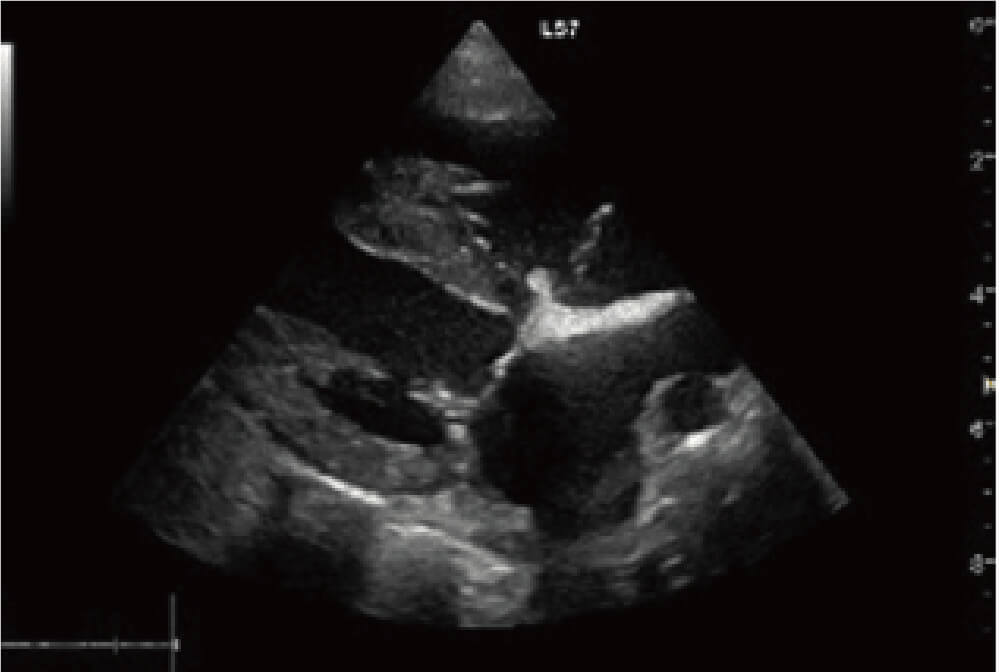

右図は僧帽弁形成術術後の画像で弁尖の位置が正常化し,前尖・後尖の良好な接合が得られたことで逆流が消失しています。